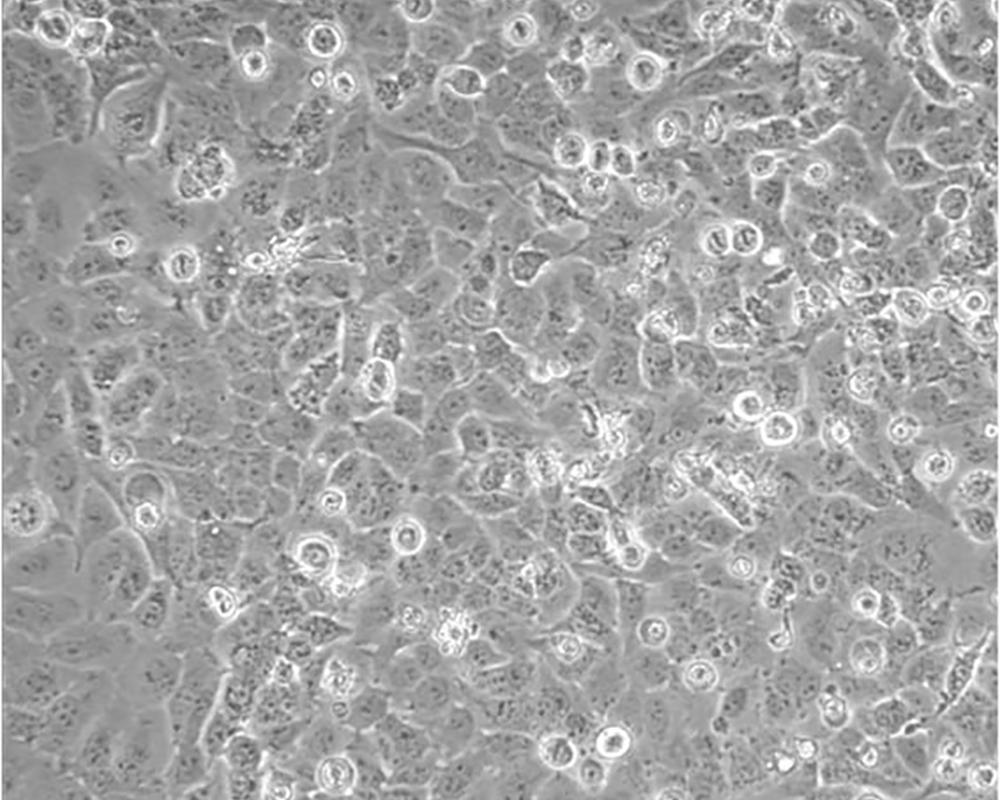

NCI-H23

產品名稱 NCI-H23

組織來源 肺腺癌;男性

細胞種屬 Homo sapiens, human

細胞污染 HIV-1、 HBV、HCV、支原體、細菌、酵母和真菌檢測陰性。

生長特性 Homo sapiens, human

培養基 RPMI-1640+10% FBS+1% P/S

形態特征 epithelial

傳代方法 1:3-1:6

細胞描述 該細胞源于一位51歲患有非小細胞肺癌黑人男性患者的治療前的腫瘤組織,表達C-myc、L-myc、v-src、v-abl、v-erb B、c-raf 1、Ha-ras、Ki-ras、N-ras RNAs;該細胞攜帶K-ras 12突變;p53基因246位密碼子突變ATC→ATG;表達PDGF A和B鏈的異源mRNA;表達TGFα、TGFβ和EGFR;角蛋白 5、8和18陽性,波形蛋白陽性,神經絲蛋白陰性,左旋多巴脫氫酶陰性;據報道,在軟瓊脂中該細胞形成克隆的效率為9.7%。